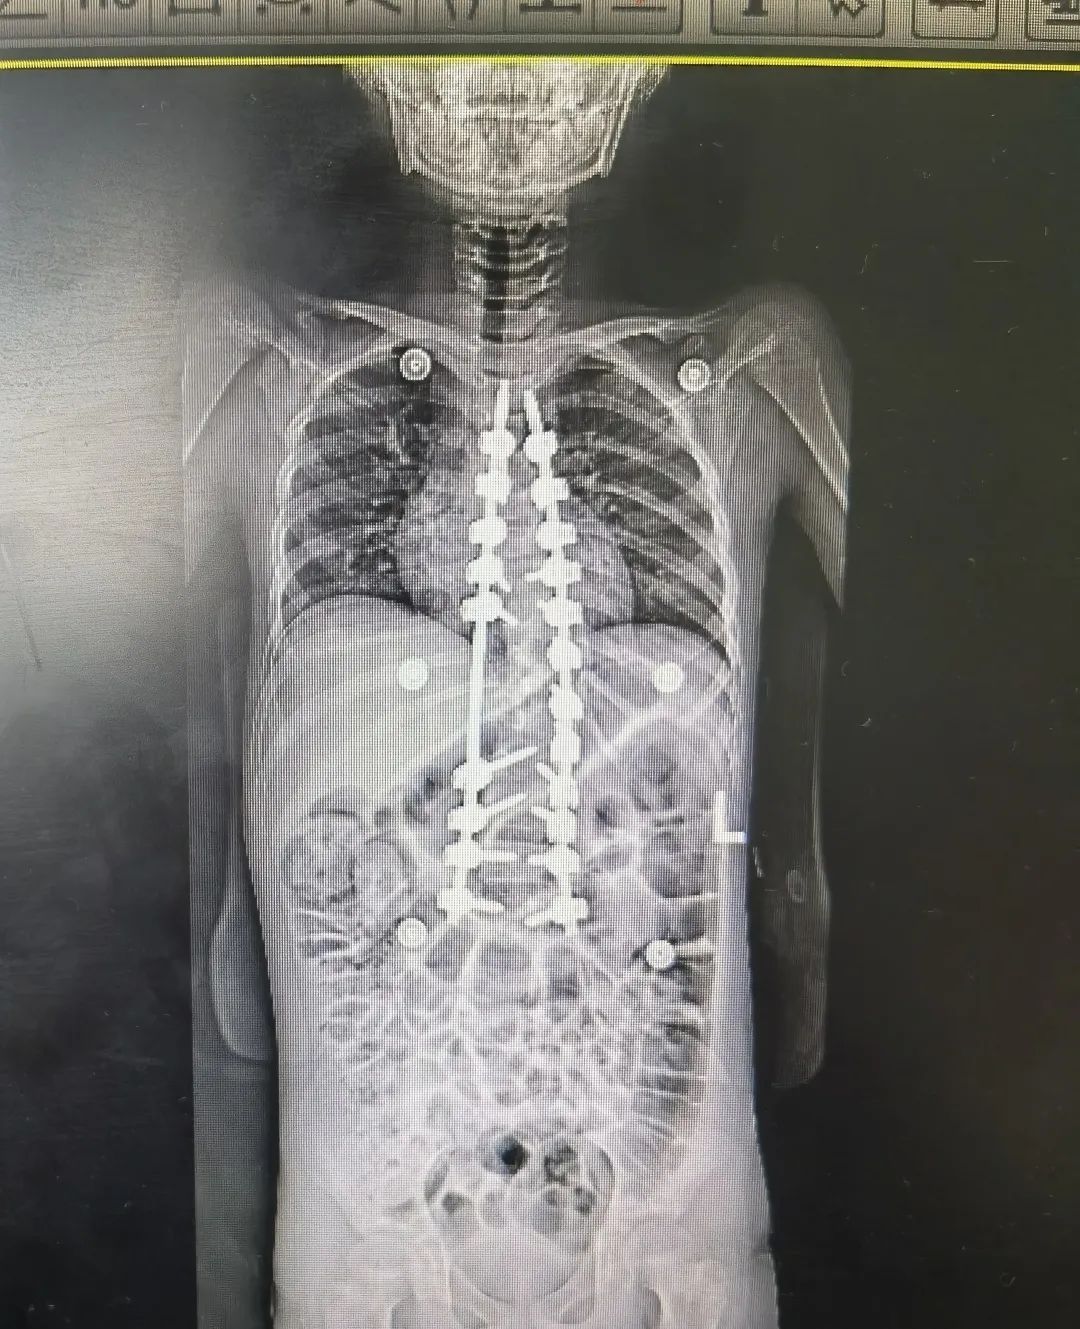

马凡综合征引起的脊柱侧弯术前术后图

“马凡综合征是一种常染色体显性遗传性结缔组织病,具有家族集聚性,可影响全身的结缔组织,有些孩子会出现脊柱侧弯的情况。”

陈文昊副主任表示,由于马凡综合征患儿骨骼发育异常,给手术增加了一定难度,但手术结果很不错的,达到了预期效果。他还指出一个自测马凡综合征的小妙招,让孩子把大拇指包住握拳,如果大拇指不能完全被包住,露出前面关节,家长就要当心了,建议去医院做进一步检查。

神经肌肉性脊柱侧弯术前术后图

克服种种不利因素,手术基本达到了既定的矫正效果,命运坎坷的玲玲在日后也能像其他孩子一样抬头挺胸。